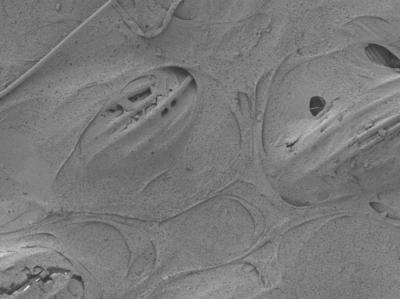

This is a closer look at the scaffolding integrated with Xuanhe Zhao’s hydrogel. The composite material, formed through a process comparable to pouring concrete over a steel framework, may be a serviceable synthetic replacement for the load-bearing cartilage found between bones. (Credit: I-Chien Liao, Frank Moutos, Brad Estes

He and Guilak began working together to integrate the hydrogel into the fabric of the 3-D woven scaffolds in a process Zhao compares to pouring concrete over a steel framework.

In their experiments, the researchers compared the resulting composite material to other combinations of Guilak’s scaffolding embedded with previously studied hydrogels. The tests showed that Zhao’s invention was tougher than the competition with a lower coefficient of friction. And though the resulting material did not quite meet the standards of natural cartilage, it easily outperformed all other known potential artificial replacements across the board, including the hydrogel and scaffolding by themselves.